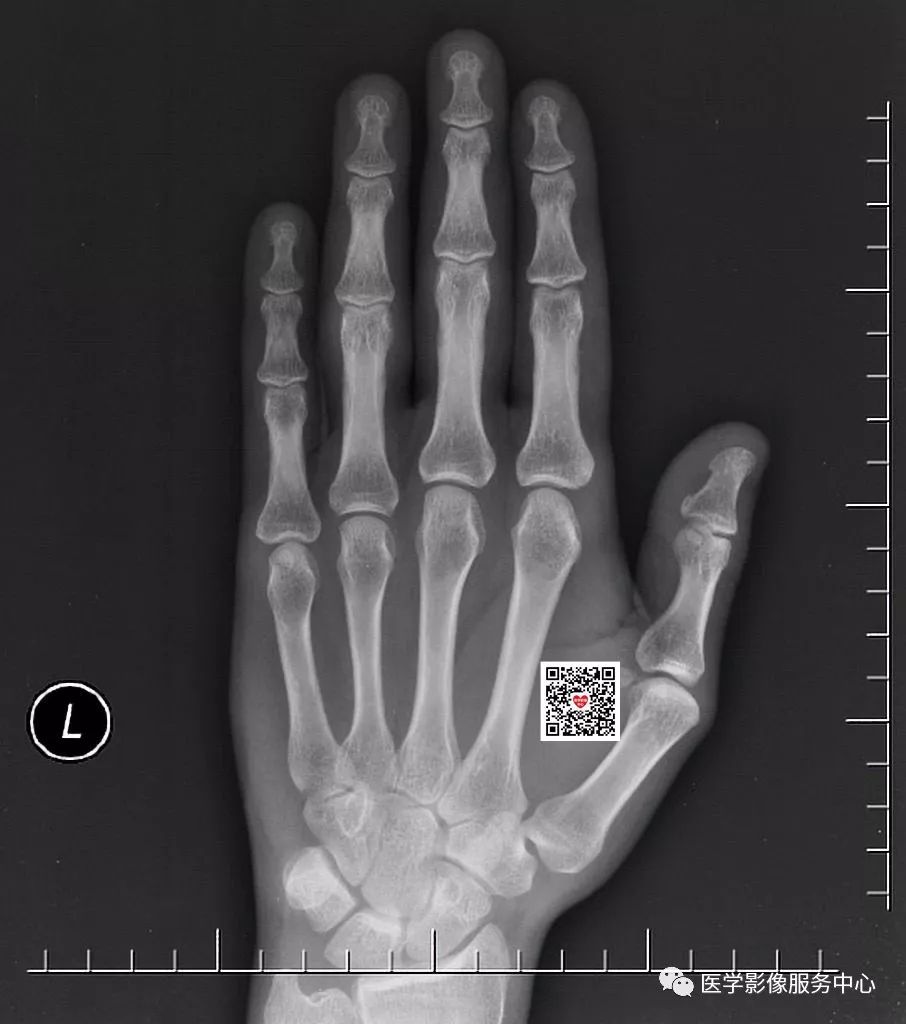

请看正位片

在这张正位片上,大家有没有发现问题?请仔细看哦!

有些外伤检查申请单上仅仅写外伤摄片,没有说明具体的受伤部位,这样的申请单是不符合规定的。以本病例来看,如果没有详细病史的话,一些经验不足的诊断医生可能会漏诊。就算有经验的诊断医生,在紧张繁忙的工作中,如果出现一丝精神倦怠,很有可能会忽略这种小的骨折线。所以,详细的检查申请单是减少漏诊误诊的必备条件。如果本病例申请单提示外伤位于左手第三指和第四指,相信大家都会重点观察受伤处并做出正确诊断。

2、标准的摄片摆位很重要

标准的摄片摆位是正确诊断的前提。但在实际工作中,由于患者伤处疼痛,往往配合不佳。这时候技术员朋友需要尽量的按照标准体位摆放,多给患者一些准备时间,不要因为可能会耽误时间而应付了事。以本病为例,正位片很难看到骨折线影,只有在斜位片才能够清楚发现两处骨折。假如患者因为疼痛,斜位摆放位置不佳,有可能将骨折线遮掩,从而得不到正确的检查结果。

一个称职的影像诊断医生,要注意影像的蛛丝马迹。本病例的正位片虽然看不到明显的骨折线影,但是第四近节指间关节周围软组织还是可以发现肿胀。斜位片更加明显,第三、第四近节指间关节周围软组织均可发现肿胀,这就给我们一个提示。这时候要仔细查看该处有无骨折存在。这种间接征象对影像诊断有很大帮助。此外,正位片看不到异常,不代表没有问题,有时我们的诊断同行正位片没发现异常,很自信的认为没有问题,匆匆扫一眼斜位片,然后直接得出未见骨折的错误诊断。正位片与斜位片都很重要,要结合看,这也是影像检查要拍摄正位及斜位的原因。